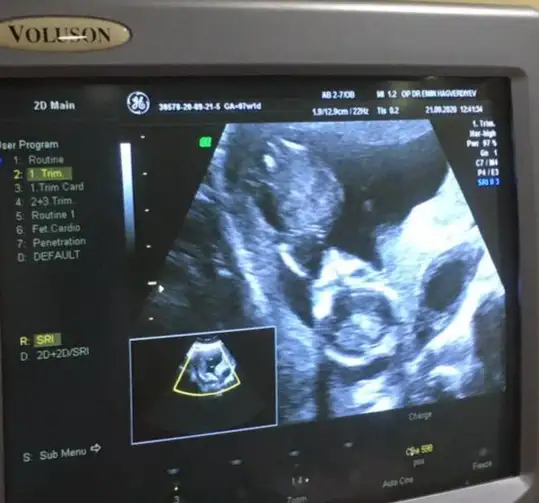

dr soylemeden siz gorun genital nub teorisi ( bebegin cinsiyeti)

Buna bakın kizmi erkekmi 🤗 size cizdim 😘

Bu da pazartesi 14+2 de gittim bunu atmadum ama amuda kalkmis resmen Sipa 😅doktor bu sefer ben sormadan tekrar erkek dedi